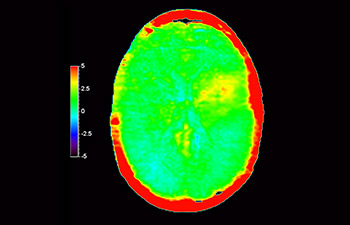

3D APT (Amide Proton Transfer) is a unique, contrast-free, brain MR imaging method addressing the need for more confident diagnosis in neuro oncology. 3D APT uses the presence of endogenous cellular proteins, to produce an MR signal that directly correlates with cell proliferation, a marker of tumoral activity. 3D APT can support trained medical professionals in differentiating low grade from high grade gliomas and, in differentiating tumor progression from treatment effect1.

3D T1w TFE 3D APT